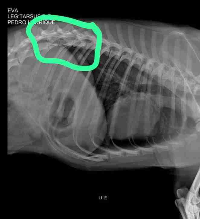

Olá tias e tios, me chamou Eva. Sou uma cadelinha de rua resgatada no dia 28.12.23.Fui atropelada 2x vezes. Uma pessoa me resgatou e me levou p uma clínica. Fiz raiox e tive uma fratura na coluna, por isso tive que ir p cirurgia urgente.Essa 1ª cirurgia no valor de (R$6.880) não deu certo infeccionou e os pinos começaram a soltar.Então tive que refazer a cirurgia com outro médico especialista que custou (R$5.000,00).Fiz meu pós operatório e logo em seguida testei positivo para cinomose.